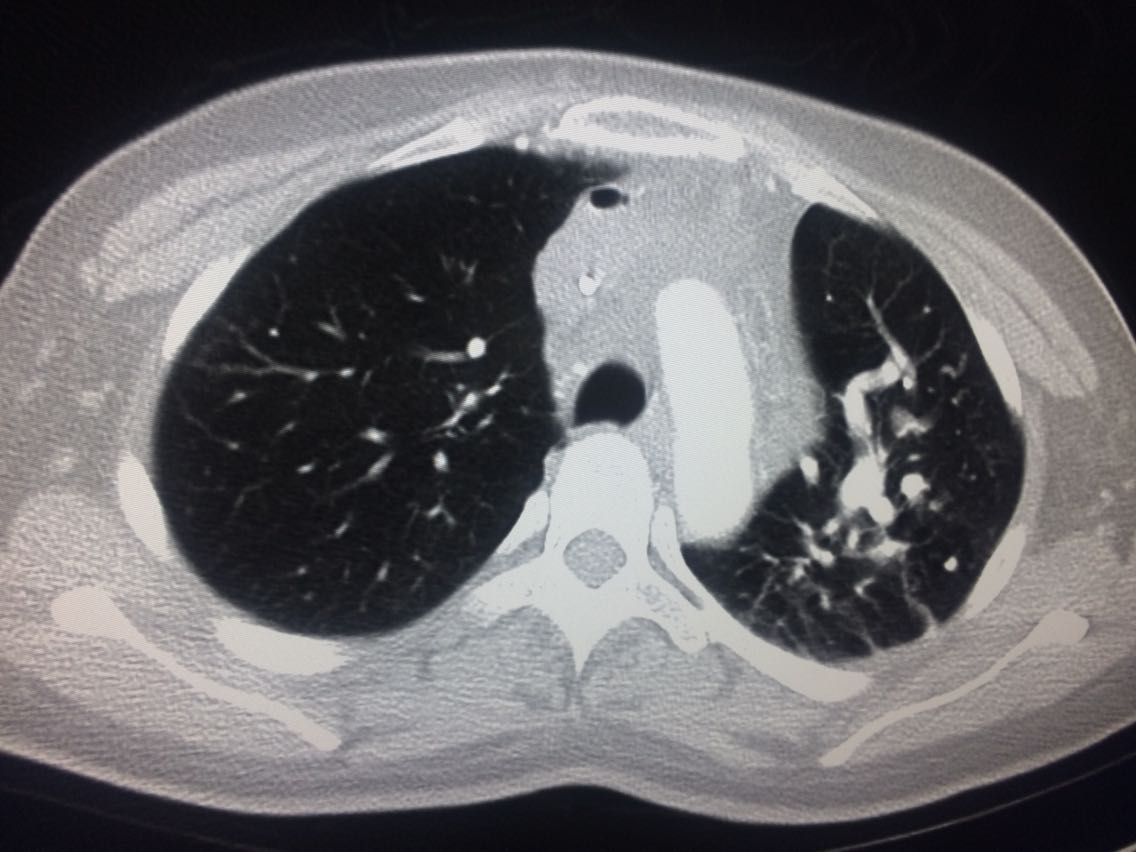

诊断,肺动脉高压。 鉴别诊断,肺动脉栓塞。 影像诊断,肺动脉高压,肺门区出现残根征,肺动脉扩张,肺动脉段膨隆,心影增大。CTA见迂曲增宽的肺动脉。 肺栓塞,影像可见典型充型缺损影,伴随肺纹理的减少。 治疗以对症处理为主,病人病史14年。 讨论诊断和鉴别诊断? 随访,症状好转。